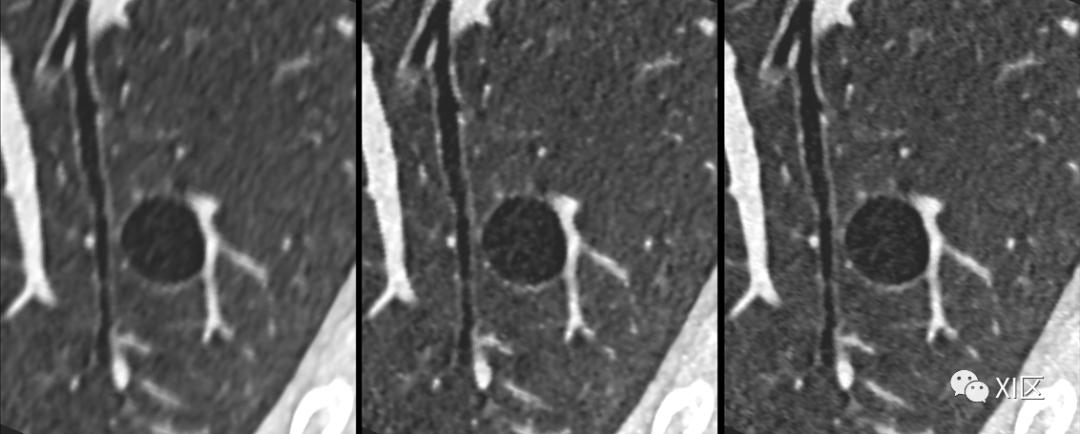

SOMATOM Force CT常规重建0.75 mm图像(左)、0.6 mm(192x0.6 mm)图像(中)与IVR重建0.6 mm(576x0.6 mm)图像(右)比较。使用IVR技术的图像肺内支气管细微结构及肺大泡显示更清晰。

SOMATOM Force CT常规重建0.75 mm图像(左)、0.6 mm(192x0.6 mm)图像(左中)与IVR重建0.6 mm(288x0.6 mm)图像(右中)、0.6 mm(576x0.6 mm)图像(右)比较。使用IVR技术的图像冠脉内钙化斑块及非钙化斑块显示更清晰。